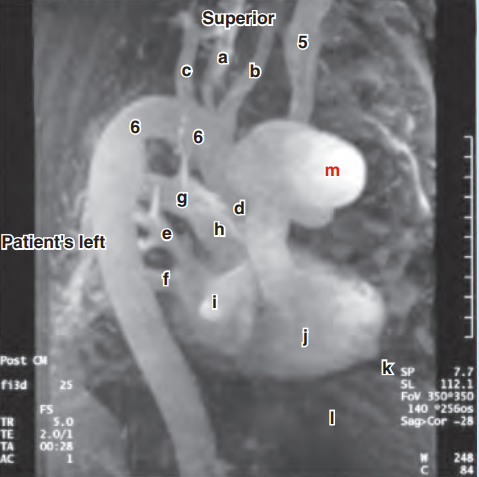

Please label the reconstructed MR angiogram